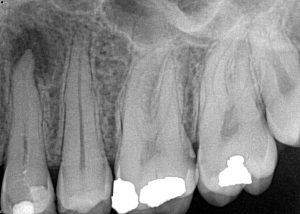

Clinical Cases